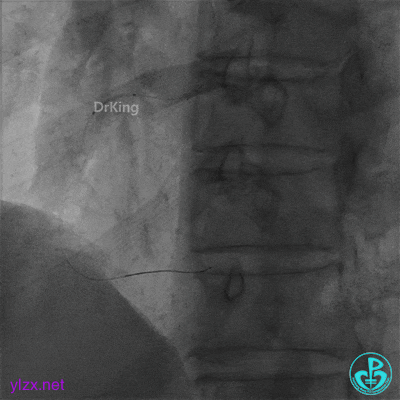

并反复经刺破球囊冠脉内静推硝普钠5次(100μg/次),右冠脉血流恢复TIMI 3级,右冠脉近端可见夹层。

支架近端植入3.5×13mm支架覆盖夹层。

最后结果示右冠脉近端支架外仍然可见夹层。